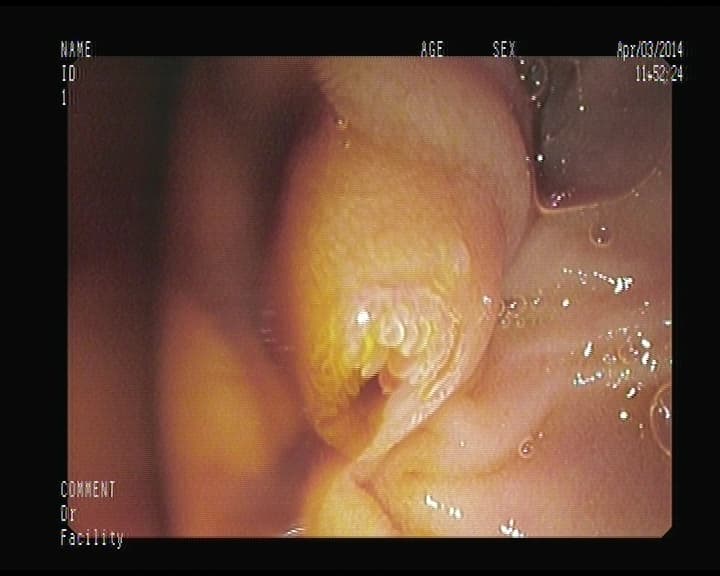

Papila de Vater

Papila de Vater drenando bilis. Allí desemboca la bilis que sale de vesícula y conductos biliares para ayudar a la digestión, en el Duodeno, primer segmento de Intestino delgado